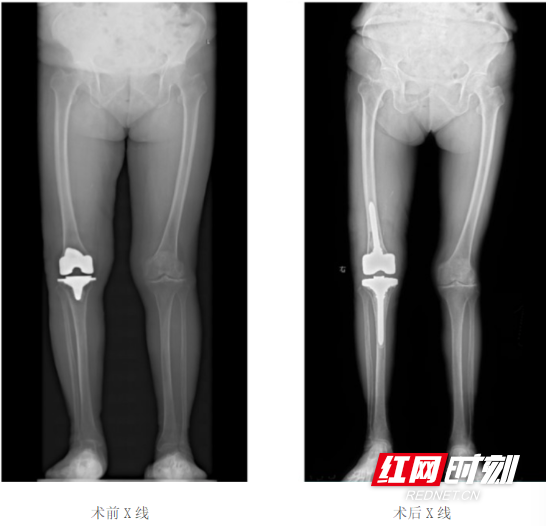

膝关节感染一期翻修:精准诊疗让老人重获行走自由

蒋阿姨右膝关节置换术后3年多,3个月前突发发热,随后出现膝关节疼痛、活动受限,辗转多地保守治疗均无明显效果,最终慕名前往郴州市第一人民医院关节外科就诊。

入院后,科室迅速为其完善检查,标本送检确诊为“甲氧西林敏感金黄色葡萄球菌(MSSA)”感染。依托成熟的感染翻修诊疗体系,科主任赵昀主任医师带领团队,联合麻醉科、手术室、药学部开展多学科协作,制定个性化手术方案,顺利实施“右膝关节感染一期翻修术”。

术后,医护团队给予规范抗感染治疗与个性化康复指导,蒋阿姨的炎症指标逐步降至正常,疼痛症状完全消失,膝关节功能稳步恢复,最终顺利出院,重返正常生活。